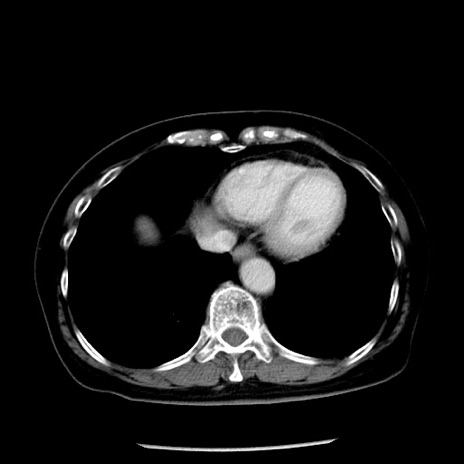

冠状断像